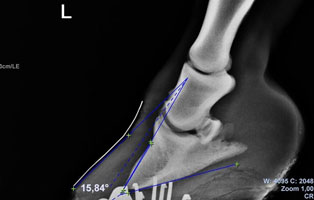

Bild: Tierärztin Karin Schmid: die starken divergierenden Linien zeigen, dass das Pony bereits sehr lange an Hufrehe leidet.